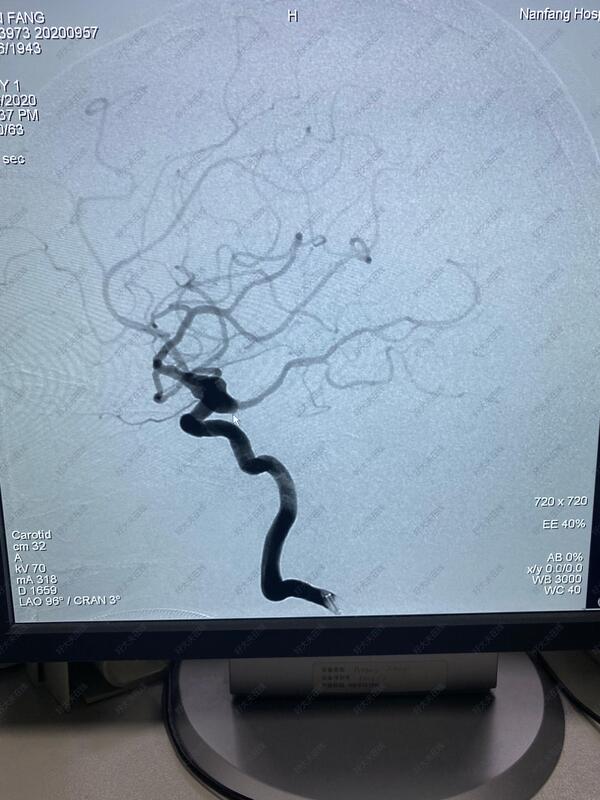

治疗中

术中采用支架辅助栓塞,保护颈内动脉和后交通动脉